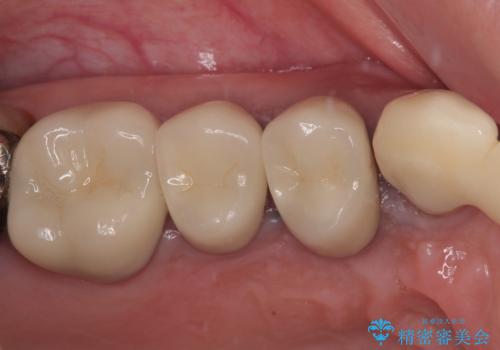

ブリッジのぐらつき インプラントを用いた奥歯の噛み合わせの再構築

歯ブラシのしやすい環境を整えるインプラント治療